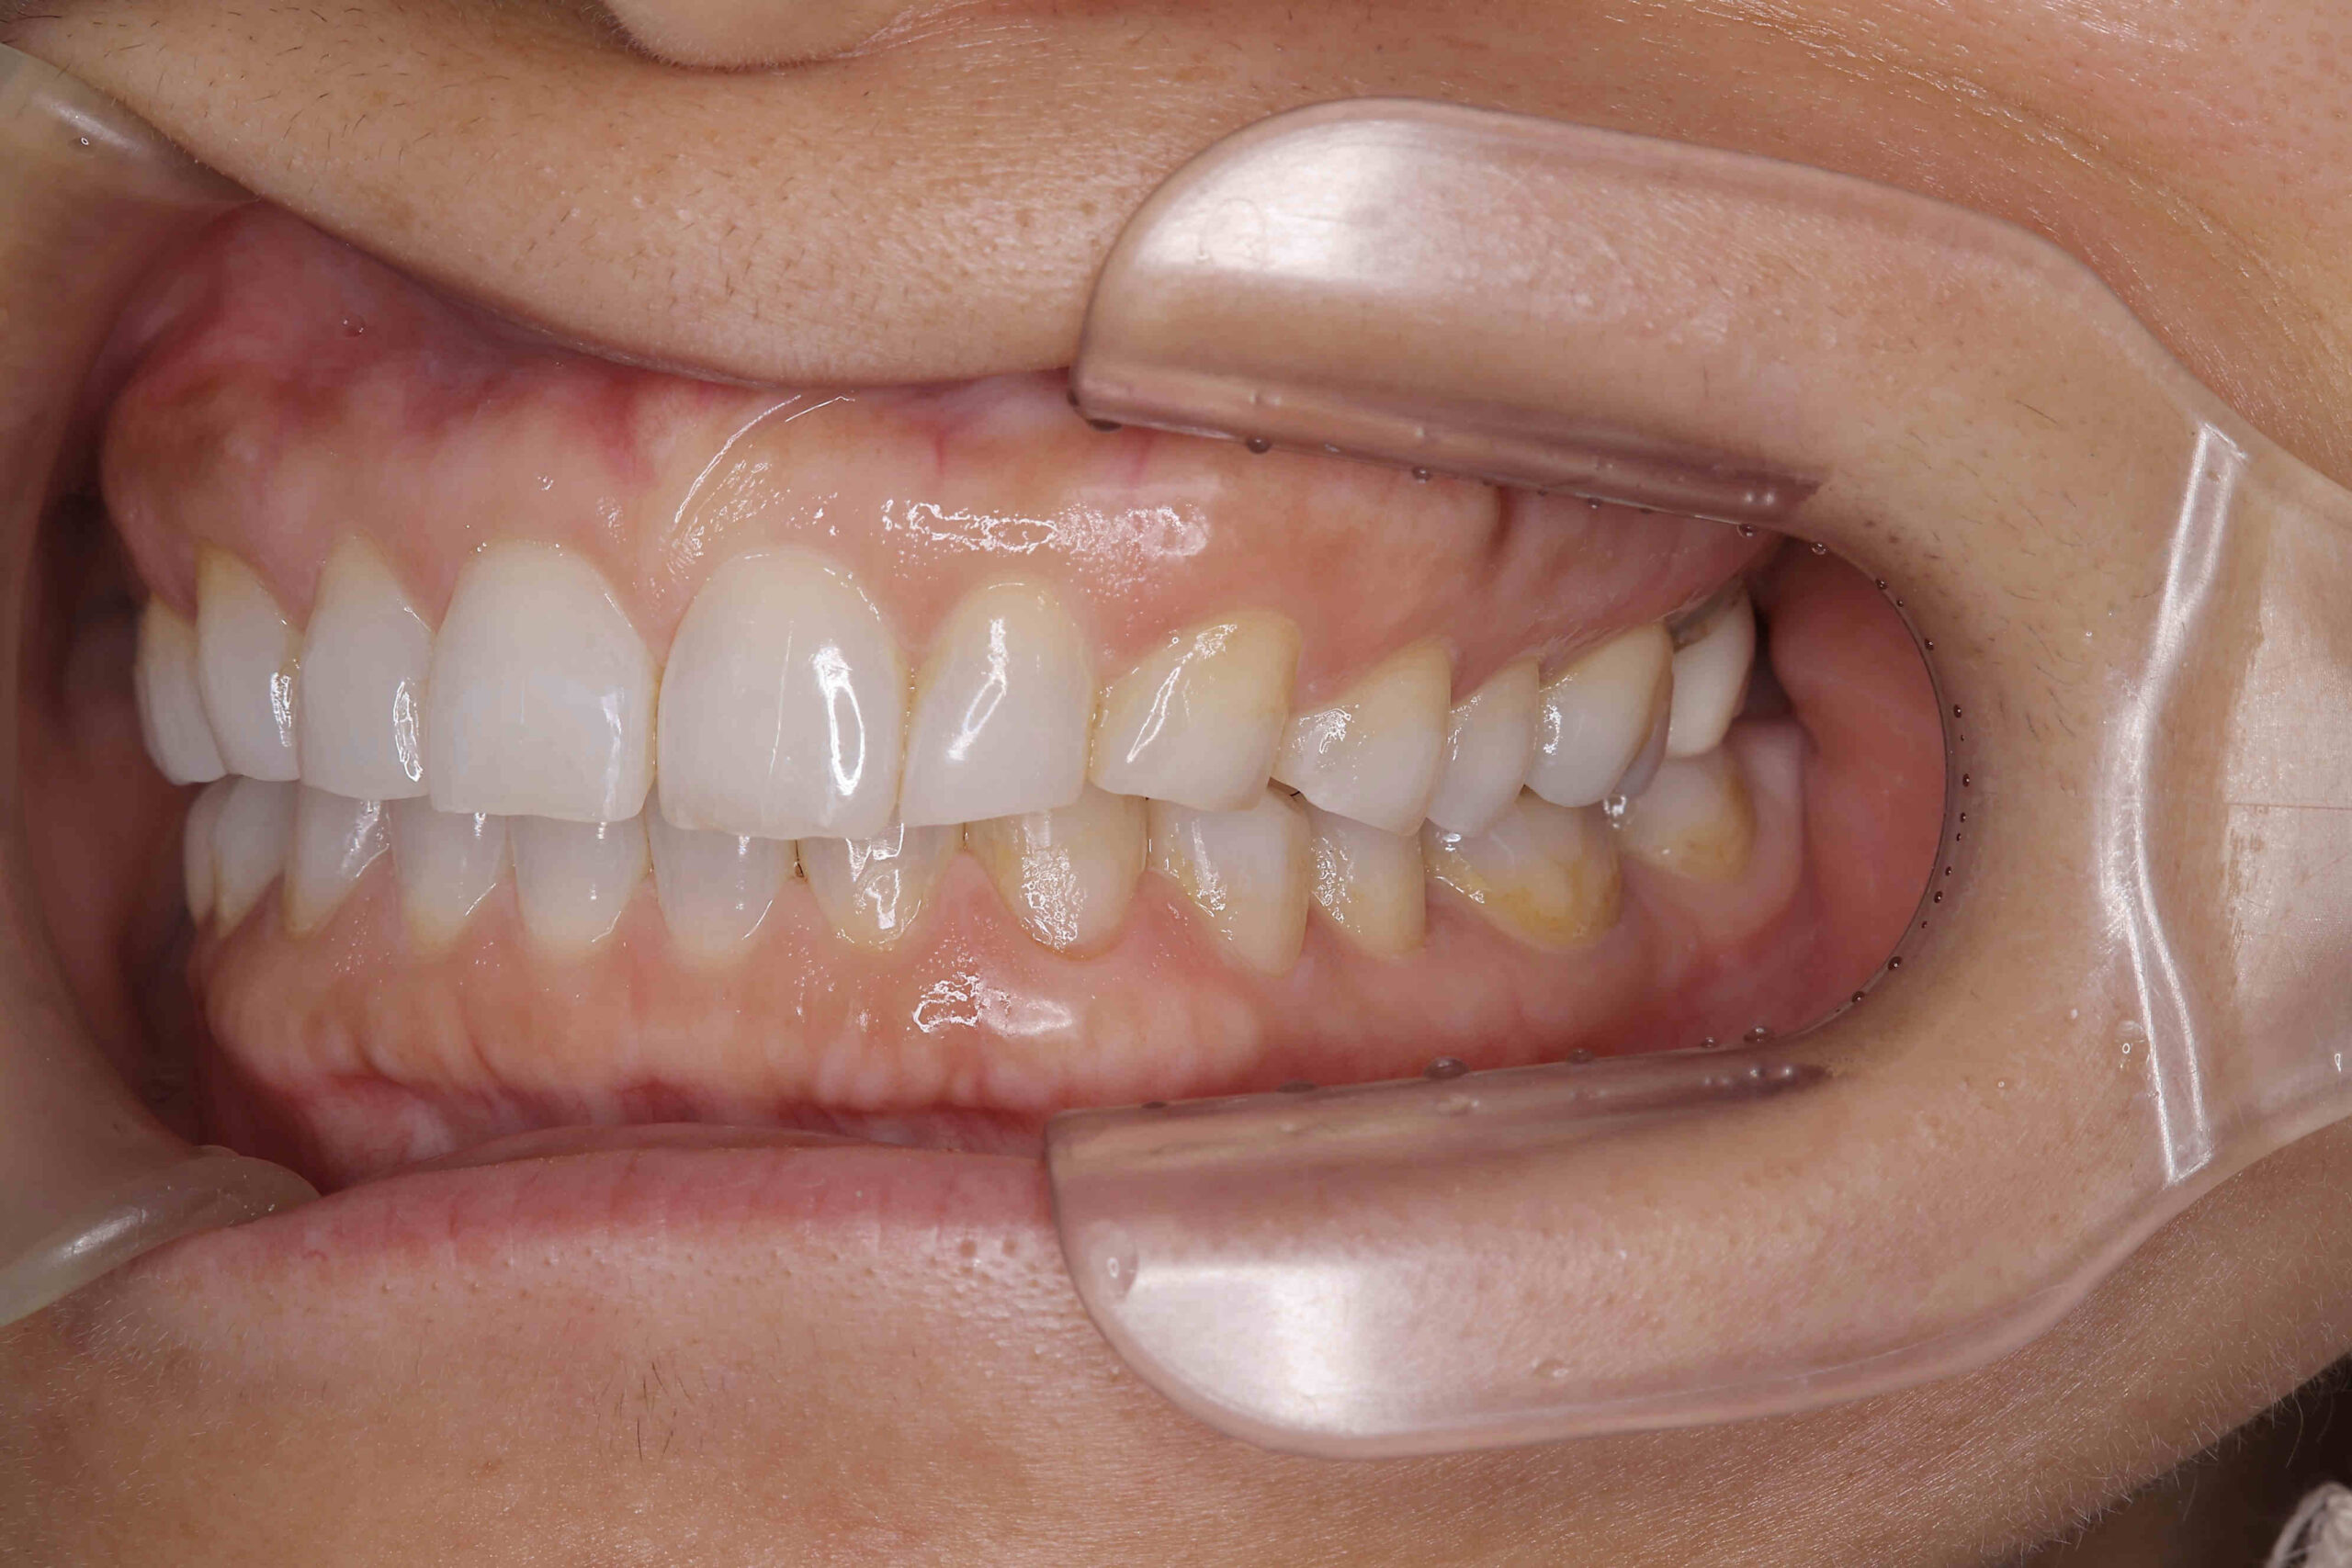

• 治療前

治療後

元々咬む筋力や食いしばり・歯ぎしりが非常に強く、『フレアーアウト』(前歯の歯並びが前方に放射状に倒れていく現象)によって「出っ歯」や「すきっ歯」の状態になっていました。

今回はご希望のマウスピース矯正で、食いしばりや歯ぎしりによる歯の破折やすり減りを予防しながら、歯と歯の隙間が広がって傾斜した前歯を元の位置に戻しました。

ホワイトニングも同時進行で施術し、白く輝く歯になりました。

元々入っていた臼歯のブリッジは治療せず、そのままの位置で矯正を行うことを希望されたため、正中(上顎と下顎の中心線)を合わせることは難しいですが、美しい歯列と口元へ仕上がりました!